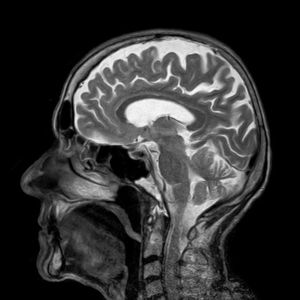

Gehirn-Röntgen: Blutversorgung verschlechtert sich.

Bild: Pixabay, toubibe